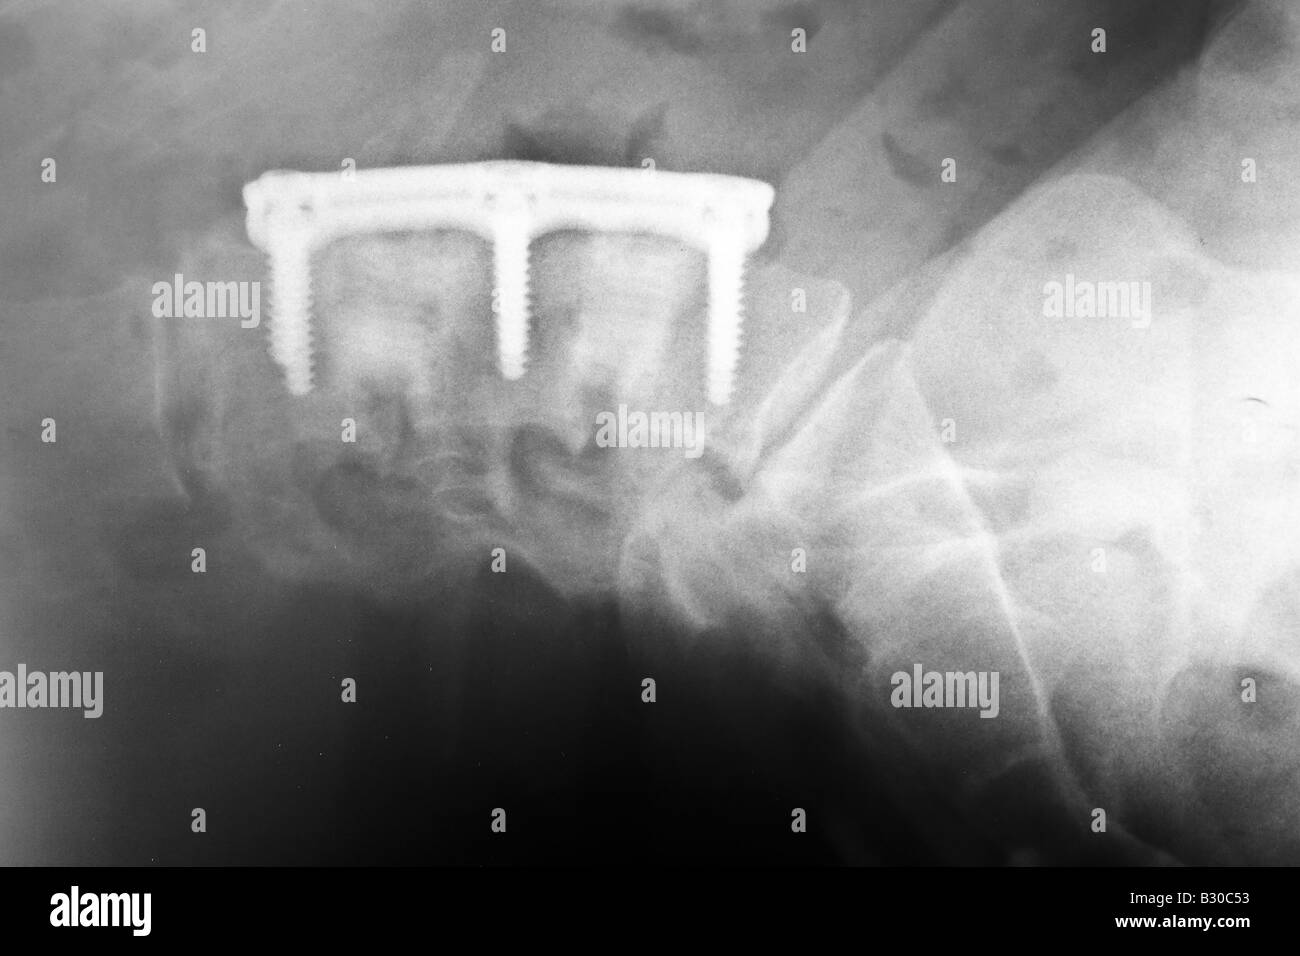

X ray of human lumber spine showing hardware used in an Anterior lumbar Hardware Failure Of Anterior Column Of Spine  Reported complications include thigh paresthesia from injury of the anterior cutaneous branch of the femoral nerve , ureter injury, pseudohernia of the abdominal. In an effort to gain an increased understanding of the need for revision surgery, the complications, and quality of life impairment associated with hardware failure, we. The earliest time to hardware failure was 1.1 months, and the. Hardware Failure Of Anterior Column Of Spine.

X ray of human lumber spine showing hardware used in an Anterior lumbar Hardware Failure Of Anterior Column Of Spine  The absence of anterior column reconstruction could result theoretically in a high incidence of hardware failure from compression fractures. Reported complications include thigh paresthesia from injury of the anterior cutaneous branch of the femoral nerve , ureter injury, pseudohernia of the abdominal. Anterior hardware impinging on anterior structures must be approached anteriorly. Patients were stratified according to the presence of. Hardware Failure Of Anterior Column Of Spine.

X ray of human lumber spine showing hardware used in an Anterior lumbar Hardware Failure Of Anterior Column Of Spine  Patients were stratified according to the presence of hardware failure. Failed posterior hardware may be approached. Anterior hardware impinging on anterior structures must be approached anteriorly. In an effort to gain an increased understanding of the need for revision surgery, the complications, and quality of life impairment associated with hardware failure, we. The earliest time to hardware failure was 1.1. Hardware Failure Of Anterior Column Of Spine.